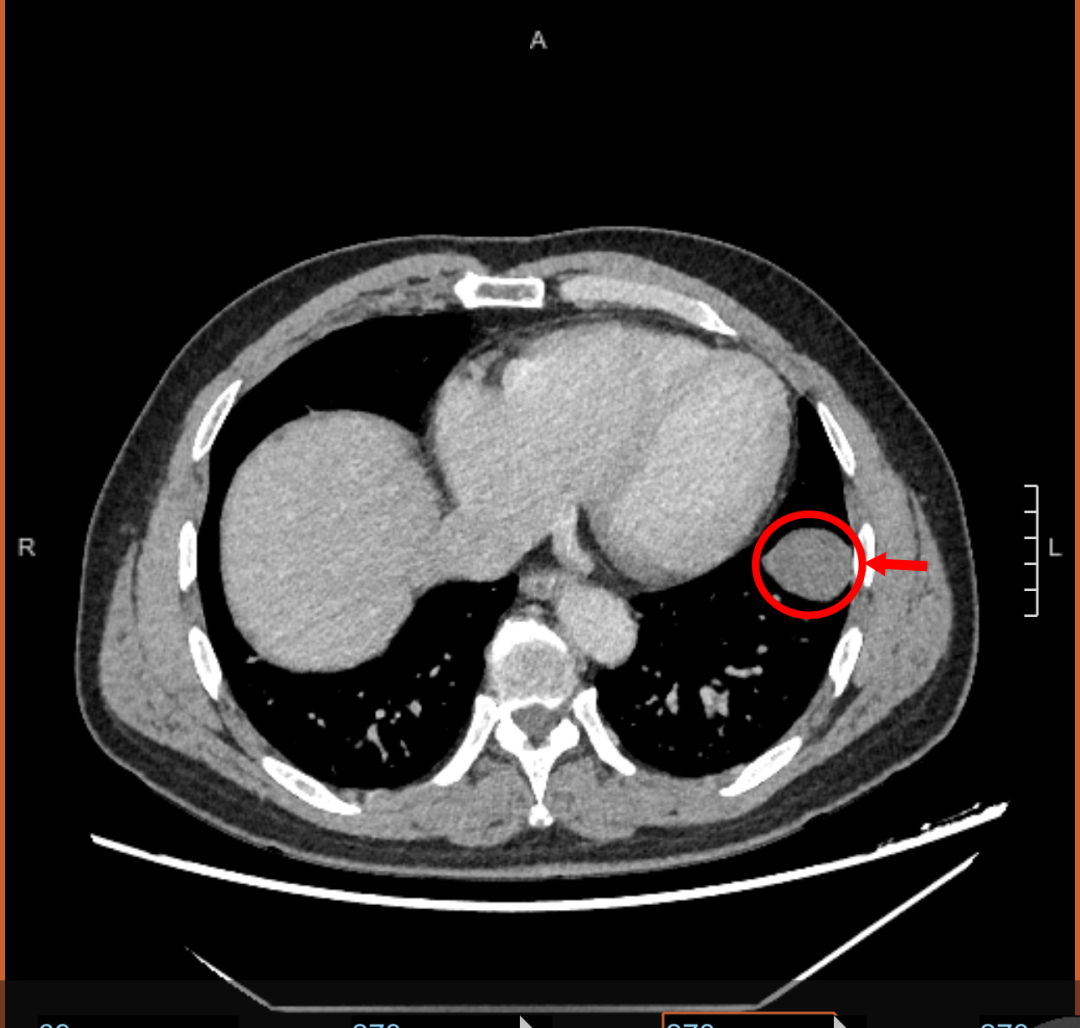

胸外科病房里的王大爷是一位刚刚退休的“健身达人”,原来每年健康查体都以“满分”通过,然而今年查体胸部CT发现其左侧胸腔有个大小4cm占位性病变,就诊淄博市妇幼保健院多番咨询后,决定住院手术治疗。

术中,胸腔镜镜发现肿瘤位于左肺下叶,手术不到1个小时顺利完成,术后病理考虑为孤立性纤维性肿瘤。此后,经过1周的综合治疗顺利出院。

“孤立性纤维性肿瘤(SFTP)是一种罕见的间叶细胞肿瘤,多为良性,少部分为恶性或交界性。”胸外科主治医师孙彬介绍,该病最常见累及部位为胸膜,也能出现在胸膜以外的组织,具有一定的遗传因素。大部分患者症状轻微,若病灶增大可出现胸闷、咳嗽等症状,主要通过胸部CT检查发现,手术切除是重要的治疗方式,完整切除的患者有良好的长期生存率。